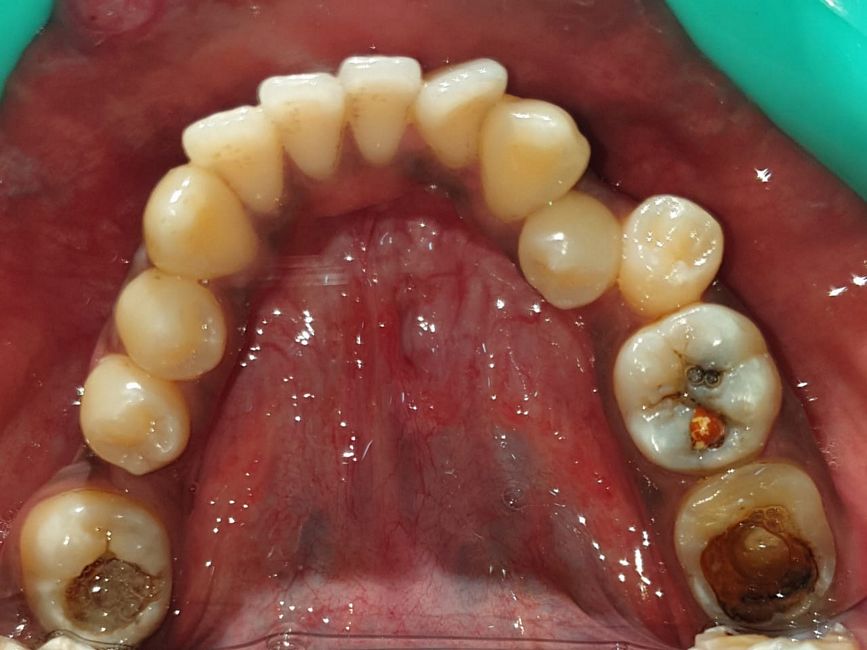

Case No: 22

Malocclusion Type: Class I Malocclusion.

Mechanics: MBT Mechanics.

Treatment: Class I Malocclusion with crowding in upper and lower anteriors treated by Non-extraction (permanent teeth)method.